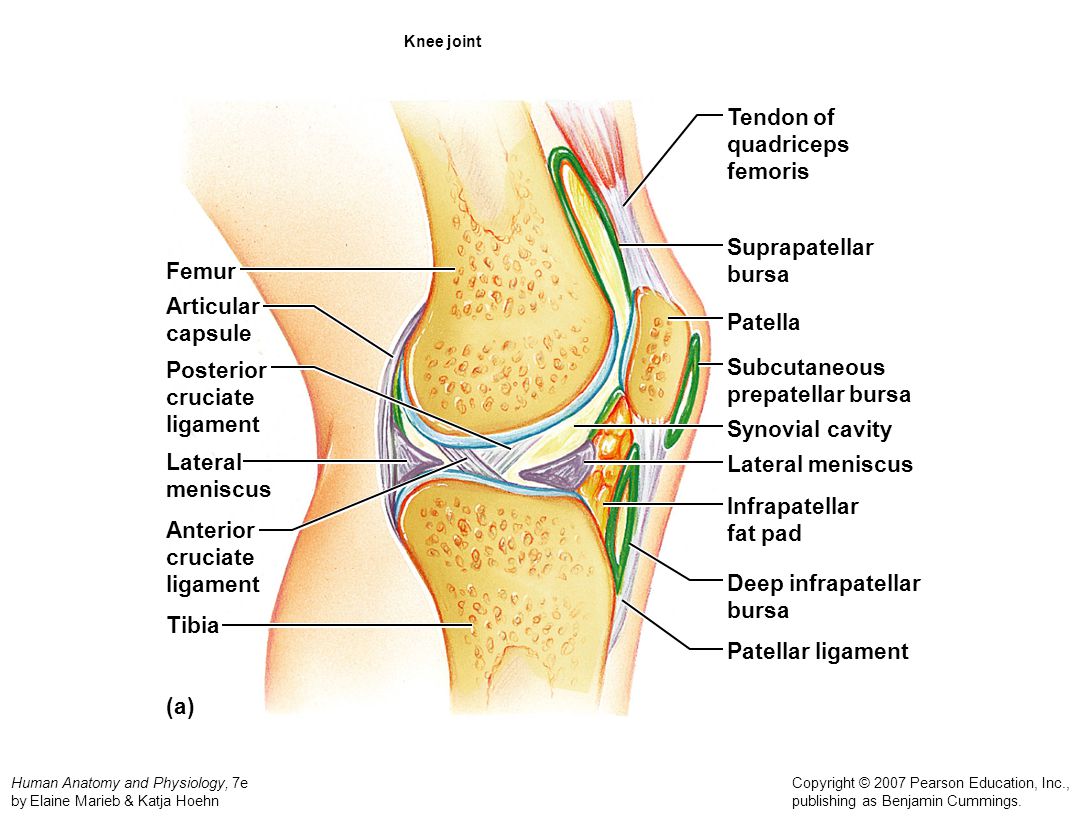

Супрапателлярный импиджмент коленного сустава: симптомы и лечение